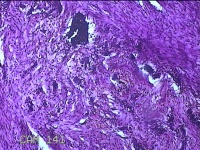

前胸部包块

性别

女

年龄

45岁

临床诊断

皮脂腺囊肿

一般病史

发现前胸部包块3个月余。

标本名称

大体所见

灰白暗红色组织2.2x1x0.8cm一块,表面带梭形皮肤2.2x1.3cm,皮下见包块1.8x1.2x0.8一块,切开包块呈实性,切面灰白粉红色,质软。

图3